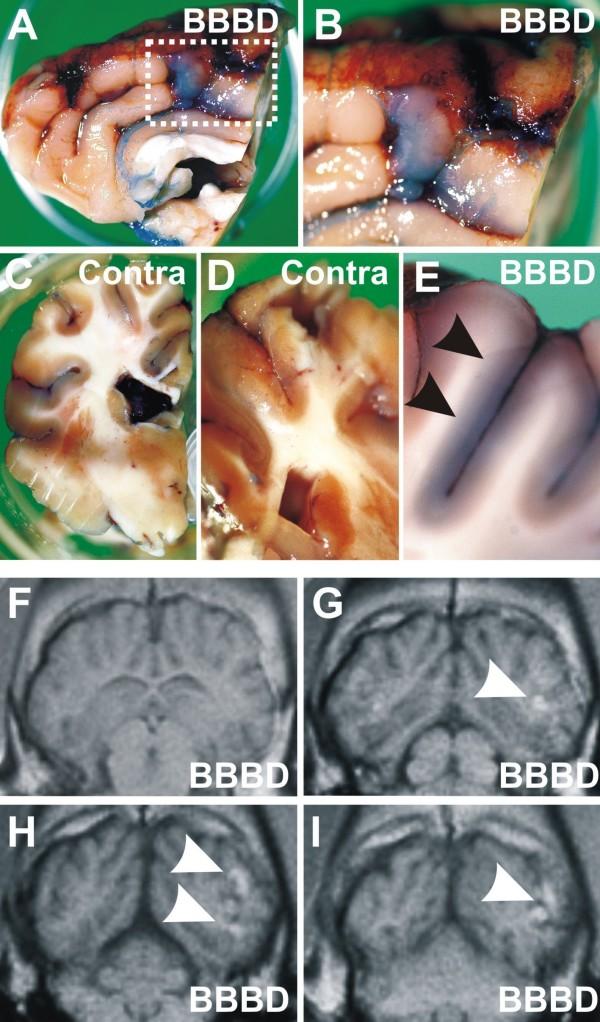

At the concentration used TALL-104 cells were tolerated. Incomplete BBBD did not allow cell entry into the brain. MRI scans at 24 and 48 hours post-injection allowed visualization of topographically segregated cells in the hemisphere that underwent successful BBBD. Perivascular location of TALL-104 was confirmed in the BBBD hemisphere by Cresyl violet and CD8 immunocytochemistry. No significant alteration in CBF or EEG activity was recorded during cell injections.

在使用的浓度下,TALL-104 细胞是可以耐受的。不完全的 BBBD 不允许细胞进入大脑。注射后 24 小时和 48 小时的 MRI 扫描允许在成功进行 BBBD 的大脑半球中可视化拓扑分离的细胞。通过 Cresyl 紫和 CD8 免疫细胞化学证实 TALL-104 在 BBBD 半球中的血管周围位置。在细胞注射过程中未记录到 CBF 或 EEG 活动的显著改变。